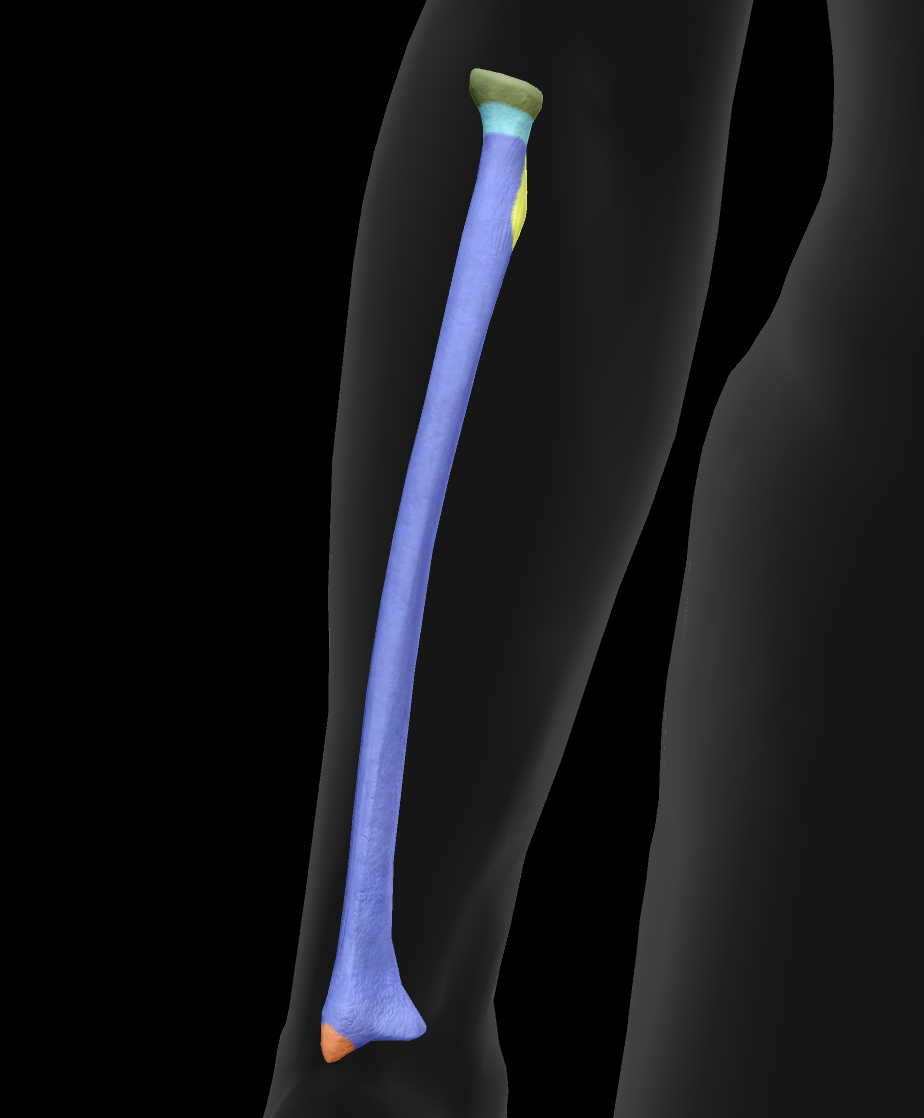

What is this bone?

radius

What is this boney landmark?

head

What is this boney landmark?

neck

What is this boney landmark?

radial tuberosity

What is this boney landmark?

shaft

What is this boney landmark?

radial styloid process

What is this boney landmark?

ulnar notch

What is this boney landmark?

lister’s tubercle